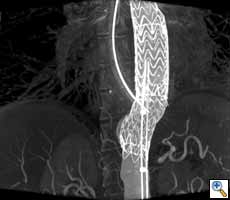

Figure

Figure 2. Aortic stent graft visualized with 3D CT-like imaging. Courtesy of Deutsches Herzzentrum Berlin, Germany Courtesy of Prof. Fosse, Rikshospitalet, Oslo, Norway.

Endovascular aortic repair

Endovascular repair (EVAR) for the abdominal aorta in chronic aneurysms has become a valid alternative to open repair with superior survival (17). EVAR is also increasingly used for the thoracic aorta (Figure 2). In selected cases EVAR in combination with open surgery is even applied for pathologies of the aortic arch and distal ascending aorta (23).